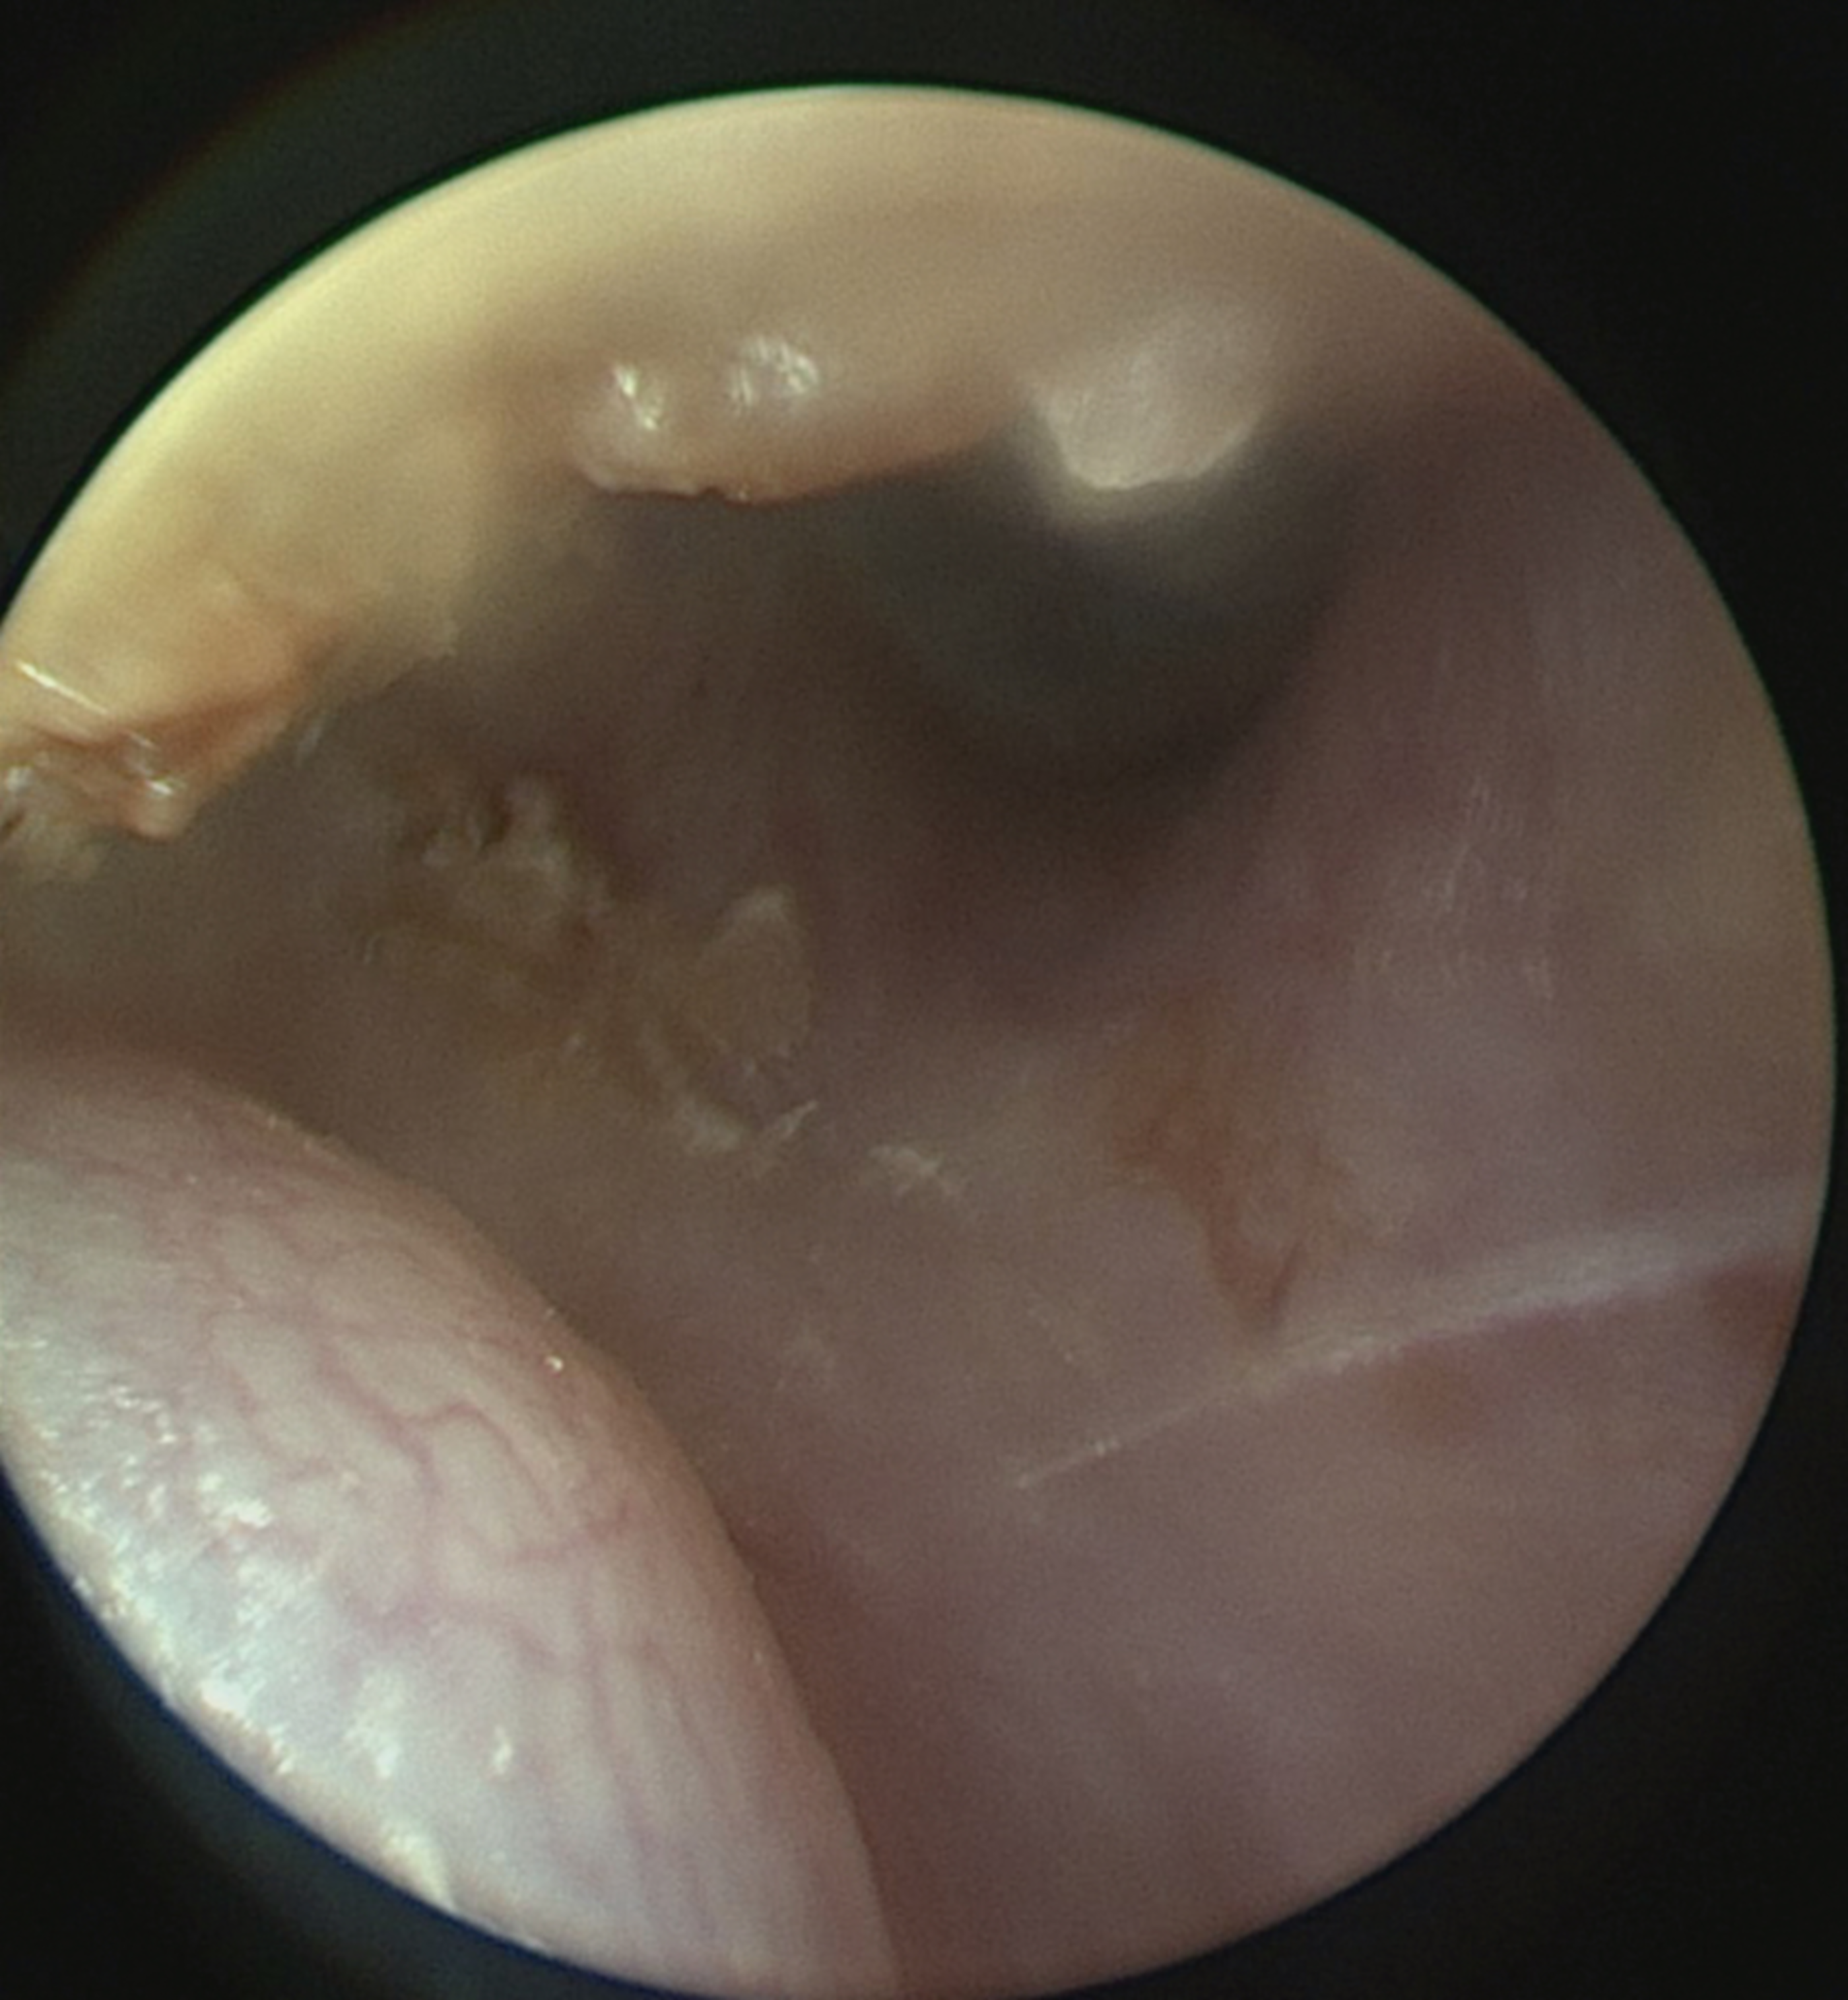

2. Presentation of Case Report

| Our case | 1/87/f | posterior | A | 13 × 10 × 6 mm | End-Exc | No rec |